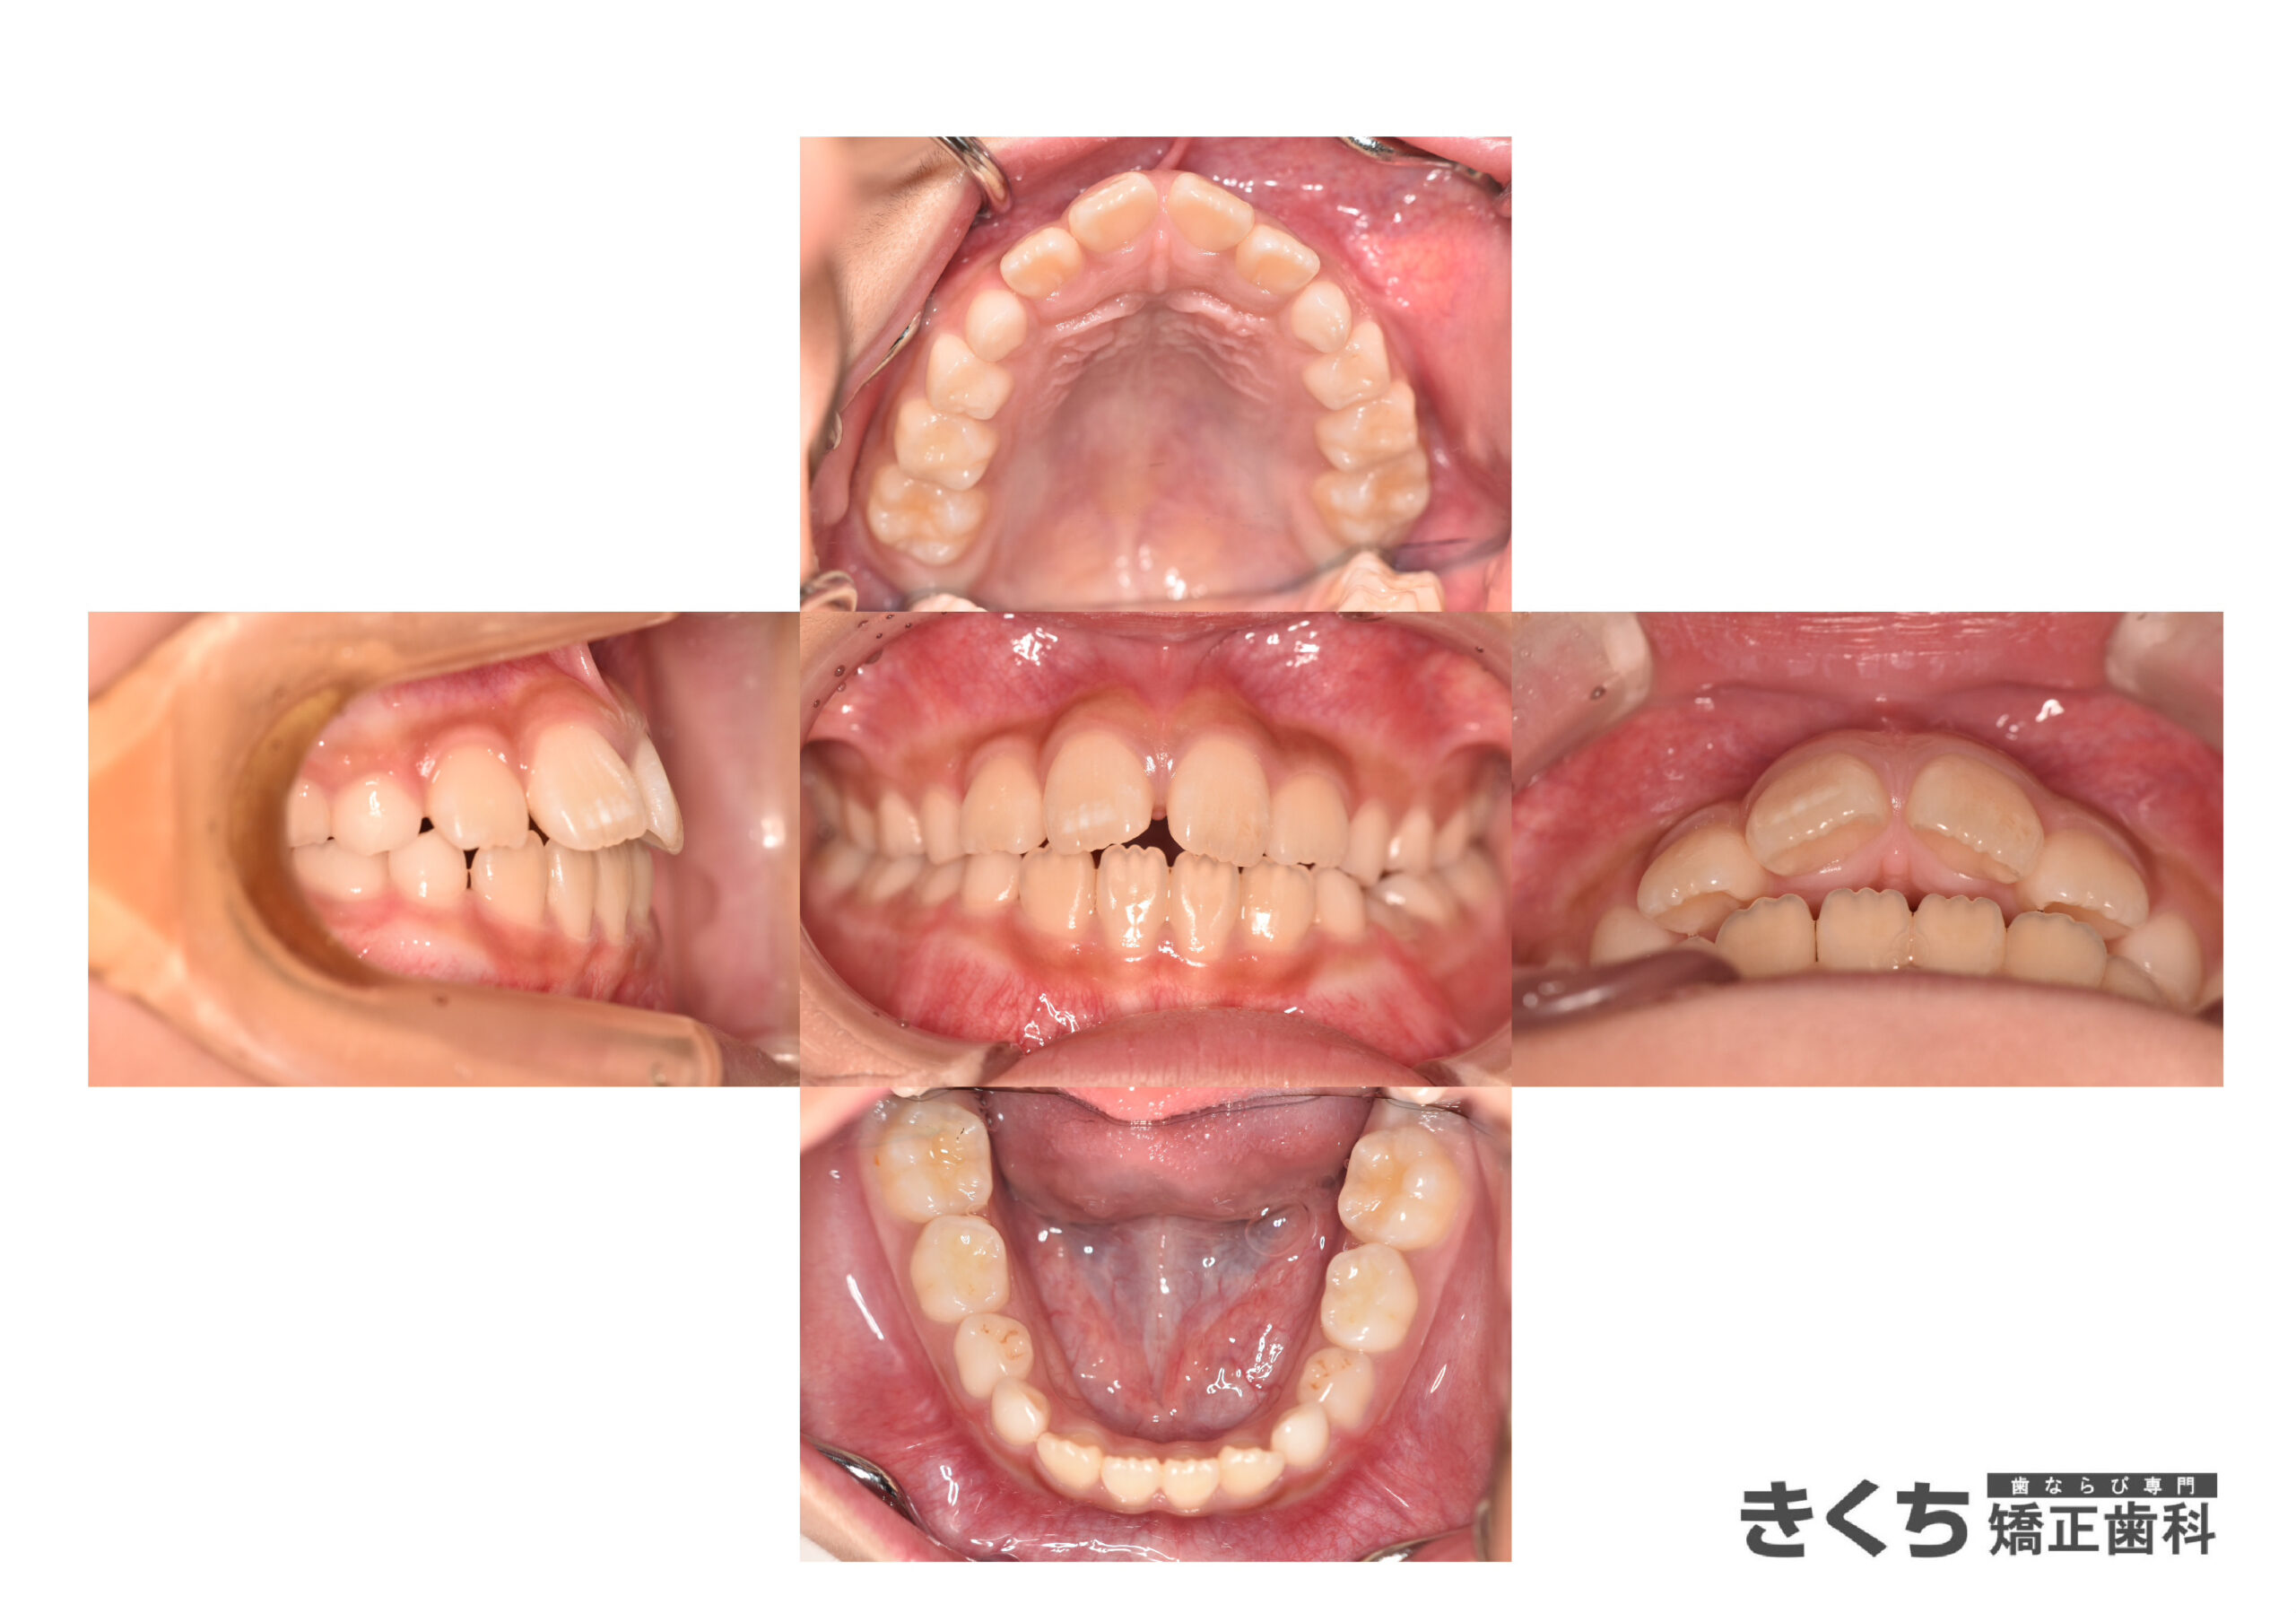

初診時7歳、かみ合わせを気にして来院

今すぐ矯正治療を始めたほうがいいと指摘を受けた

→6ヶ月ごとのペースで経過観察

口腔筋機能を改善するために指導を行いました。

↓↓↓↓↓↓↓ 6ヶ月後